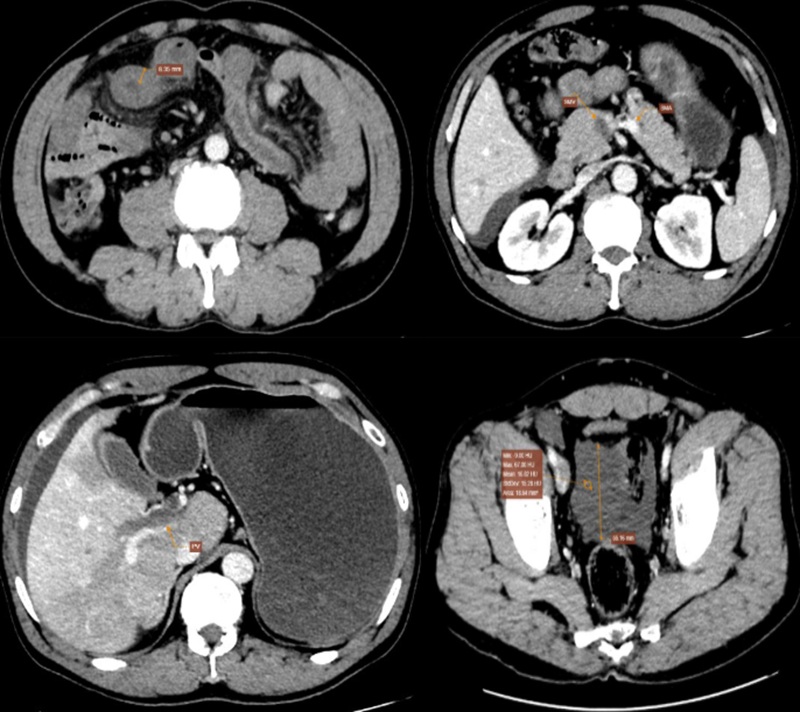

Kết quả CT xác định: Nhồi máu ruột non vùng thượng vị quanh rốn, nghi ngờ có bóng khí trong thành ruột do hoại tử; huyết khối tĩnh mạch cửa và tĩnh mạch mạc treo tràng trên, theo dõi huyết khối tĩnh mạch chủ dưới, tĩnh mạch chậu và tĩnh mạch đùi chung hai bên; có dịch tự do ổ bụng.

Hình ảnh chụp cắt lớp vi tính có tiêm thuốc cản quang của bệnh nhân

Từ các kết quả trên, bác sĩ chẩn đoán, bệnh nhân mắc nhồi máu ruột non do tắc tĩnh mạch mạc treo tràng trên và tĩnh mạch cửa, đã biến chứng hoại tử ruột. Người bệnh nhanh chóng được chuyển tuyến can thiệp phẫu thuật cắt bỏ đoạn ruột hoại tử do thiếu máu. Nhờ xử trí kịp thời, sau phẫu thuật, tình trạng bệnh nhân ổn định dần, phục hồi tốt và đã được xuất viện.